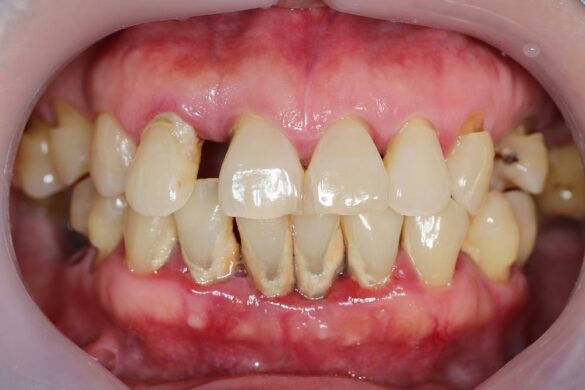

Gum disease, in its mildest form, often begins with the buildup of plaque on the teeth and gums. Several risk factors can increase the likelihood of developing gum disease, including poor dental hygiene, signs of gum disease such as bleeding or swollen gums, and a history of tooth decay. It’s crucial to address these risk factors promptly to prevent the progression of gum disease and maintain healthy teeth. Regular dental check-ups and proper oral care routines play a vital role in reducing the risk of gum disease and preserving overall oral health.

Tooth loss can be caused by various factors, with gum disease being a significant contributor. This condition often progresses through different stages, starting with soft tissue inflammation and leading to more severe symptoms of gum disease. Family history can also play a role, as genetics may predispose individuals to a higher risk of developing gum disease. However, dental care and regular check-ups are essential in managing and preventing gum disease. By addressing the early stages of this condition and maintaining good oral hygiene habits, individuals can reduce the risk of tooth loss and ensure the long-term health of their teeth and gums.